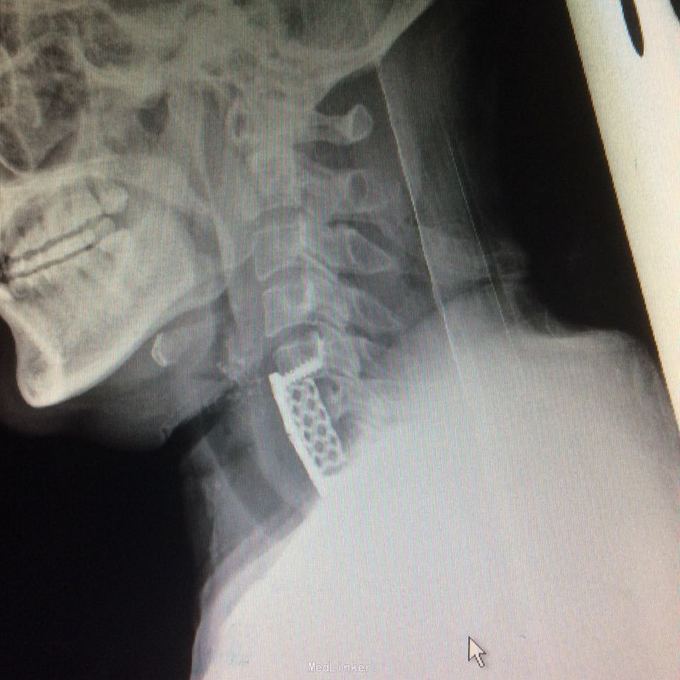

混合型颈椎病 前路act

患者压迫解除及时,术后恢复满意